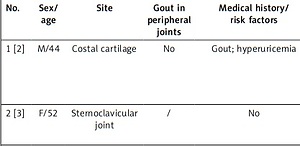

Involvement of anterior chest structures accompanied with chest pain in patients with gout

Arch Med Sci 2023;19(2):532-535